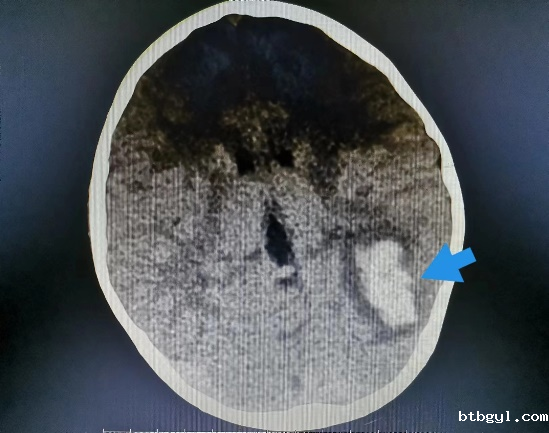

近日,一向身体健康的8岁的小男孩小阳(化名),几天前突然开始剧烈头痛,反复恶心、呕吐,奶奶赶紧把他送到我院就诊。 起初,大家认为小阳只是简单的感冒或则肠胃问题,普通检查没有找到病因,最终在颅脑CT提示下发现小阳“左侧枕叶脑出血伴血肿形成”。 患儿入院影像(左图为颅内出血、右图为胸腔积液及心包积液) 入住神经外科后,考虑到小阳近期并没有受过外伤,依据既往经验,小阳的脑出血可能是先天性血管畸形,但完善相关脑血管检查后却提示小孩脑血管正常,诊断一时陷入了僵局。 仔细问诊 查找蛛丝马迹 经过不断询问,副主任医师汪棋笙了解到小阳来自山区农村,且平时有喝生水和吃生螃蟹的习惯,汪棋笙似乎找到了诊断的关键。回顾了小阳血常规结果嗜酸性粒细胞较正常增高4倍,结合患儿心肺CT提示心包积液、胸腔积液,存在多器官损害表现,汪棋笙高度怀疑小阳就是肺吸虫感染、脑型肺吸虫病。 多方打探 从成都邀请工作人员上门检测 近年来肺吸虫病感染率非常低,肺吸虫血清抗体检测在周边各大医疗中心均已停止开展此项检查,诊断再次陷入困难。经多方打听,最终联系到可以开展此项检测的机构,为此,科室立即联系,邀请工作人员从成都赶来上门抽血检测。最终确立了肺吸虫感染、脑型肺吸虫病的诊断。 寻遍全省 获得特效药 尽管小阳的诊断已明确,可新的问题又再次出现,治疗肺吸虫的特效药物“吡喹酮片”医院及市场上已经无法购得。科室可谓是全员出动,寻遍各级医疗机构,最终从四川省疾控中心获得该药物,治愈了小阳。 患儿出院影像(颅内出血、胸腔积液及心包积液已基本吸收) 特别提醒: 饮用生水或吃了未经煮熟的青蛙、蛇等肉类,容易导致寄生虫感染,寄生虫可进入血管,并通过血液循环进入大脑内生存,引发相关脑病。 肺吸虫是什么? 肺吸虫又称并殖吸虫,是甲壳类哺乳动物的常见人兽共患寄生虫。当它们在组织中迁移时会引发嗜酸性反应,因此我们可以在化验单上看到嗜酸性粒细胞增多。肺吸虫感染人体后主要寄生于肺部,还可异位至脑部、腹部及皮下等部位,引起相应的器官组织病变。 哪些习惯容易招虫? 近年来发病率有所下降,但在部分人或因饮生水、生食或者半生食虾蟹的习惯,导致该病时有发生。 如何预防肺吸虫感染? 1.不要随意喝生水,尤其是河水、小溪水等。 2.切勿吃生的淡水螃蟹、小龙虾等,一定要煮熟。 3.避免食用未煮熟的其它淡水甲壳类动物或来自污染水源的淡水鱼类。 神经外科联系电话:0830-5216264